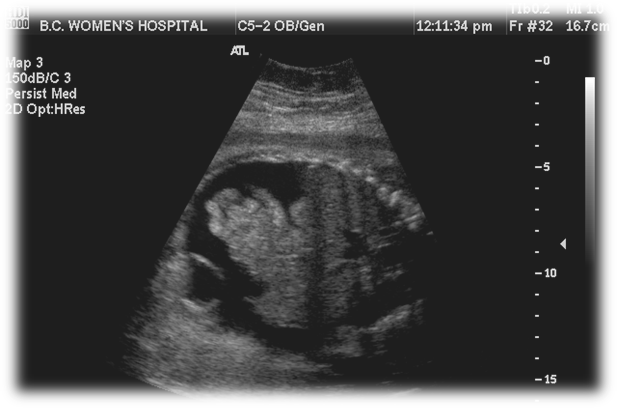

What is Ectopic Cordis?

Abnormal development of primitive heart OUTSIDE the embryonic disk

Stemming from a ventricle wall defect

Ectopic Cordis